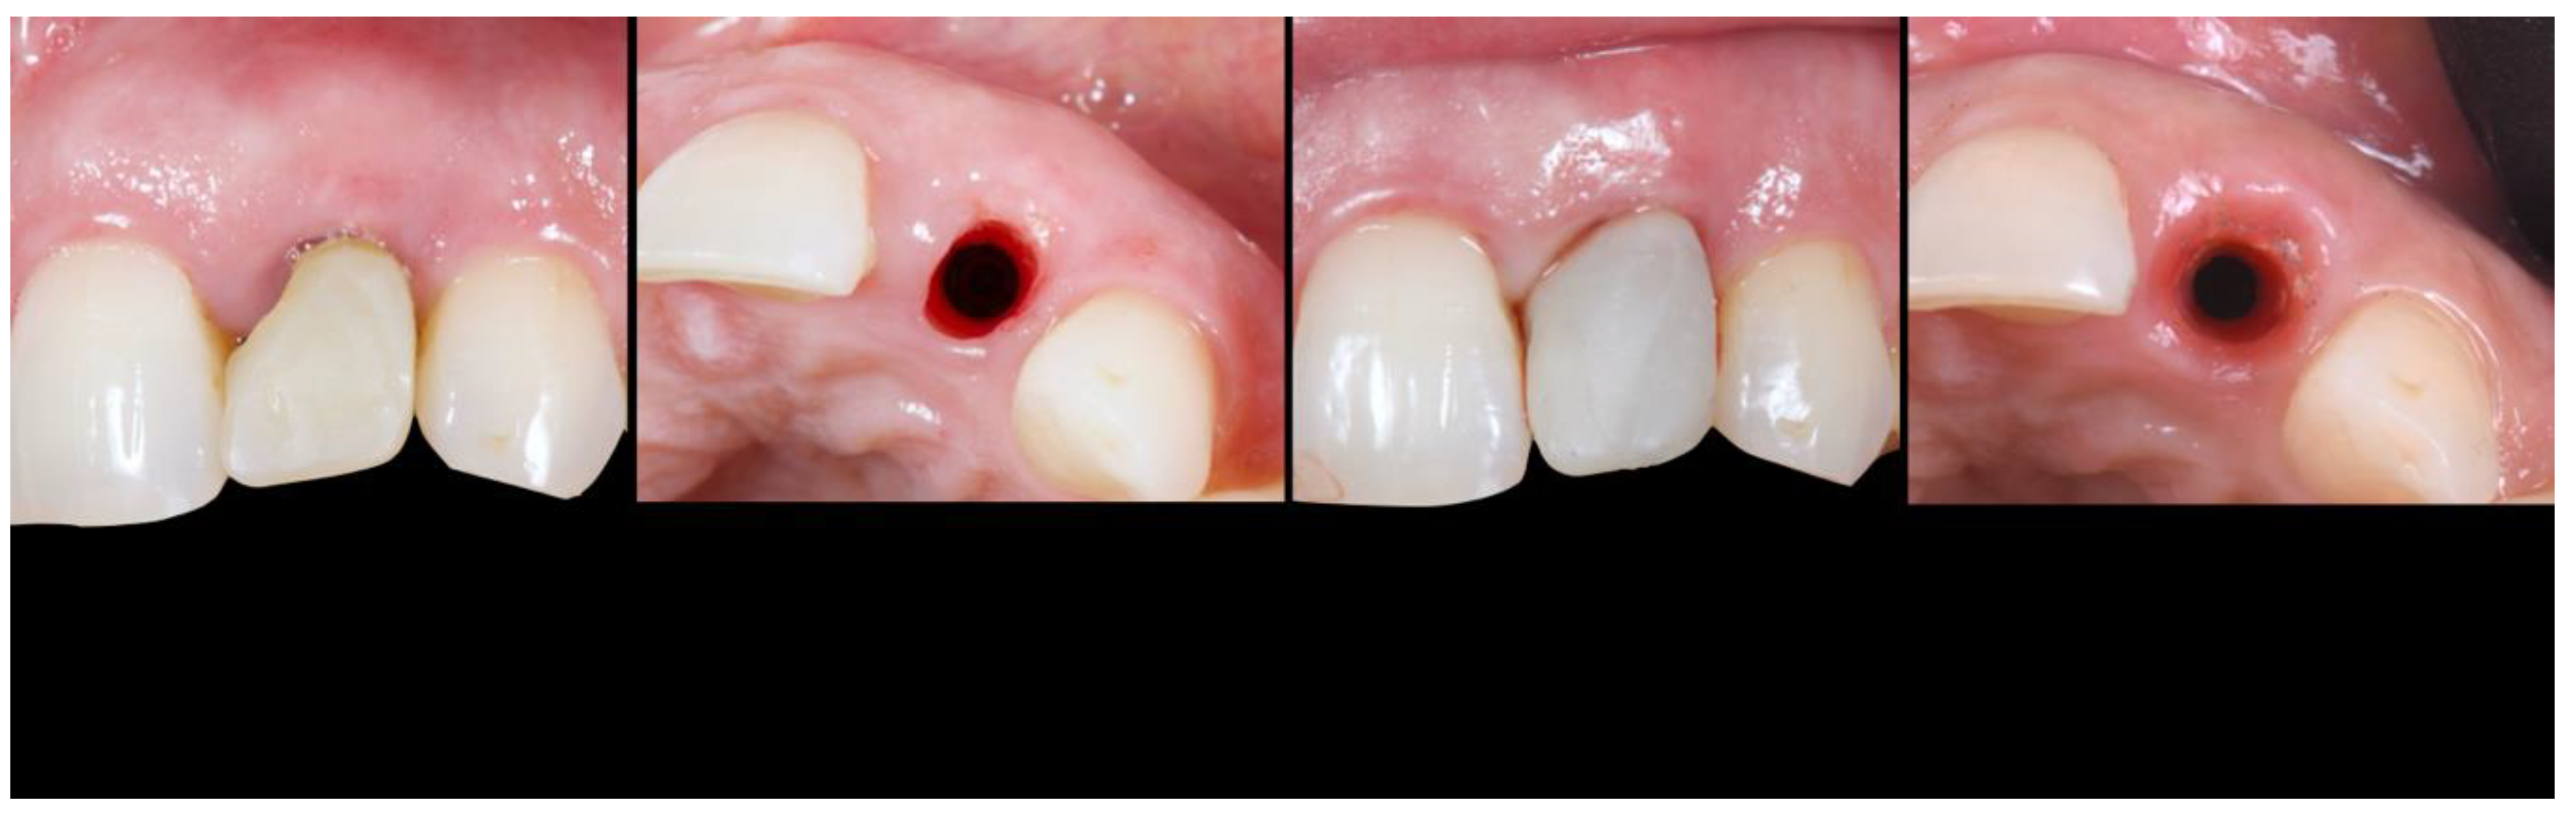

- (A)

- Supra-periosteal pouch design, demonstrating proper lateral and vertical extensions. The red lines demonstrate the pouch, while the yellow line demonstrates the mucogingival junction.

- (B)

- First abutment in place and membrane adaptation prior to BRG introduction.

- (C)

- Final relationship between first temporary prosthesis, abutment, and cervical gingival tissue.